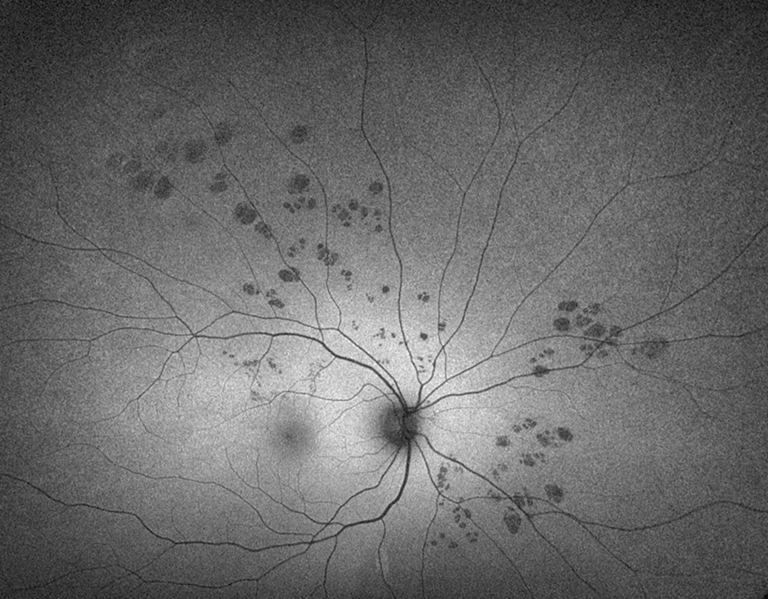

Bear Tracks

Presented by Sean Grout, OCT-CThis photograph received Honorable Mention in the category "Fundus Autofluorescence" and was displayed at the 2024 ASCRS/OPS Society Exhibit.